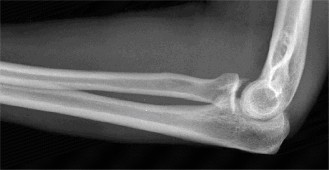

It should be noted that reverse total shoulder arthroplasty is also the procedure of choice in patients with cuff-tear arthropathy (aka rotator cuff arthropathy). Characteristics of cuff-tear arthropathy include superior migration of the humerus due to a massive rotator cuff tear, glenohumeral joint destruction, subchondral osteoporosis, and humeral head collapse (see Fig. 2–17). A reverse total shoulder

Figure 2–17_X-rays of a patient showing evidence of cuff tear arthropathy. The humerus is migrated superiorly, the glenohumeral joint is destroyed, there is subchondral osteoporosis, and the humeral head is collapsed. (From Ecklund KJ, Lee TQ, Tibone J, Gupta R. Rotator cuff tear arthropathy. _J Am Acad Orthop Surg. 2007;15(6):340–349.)